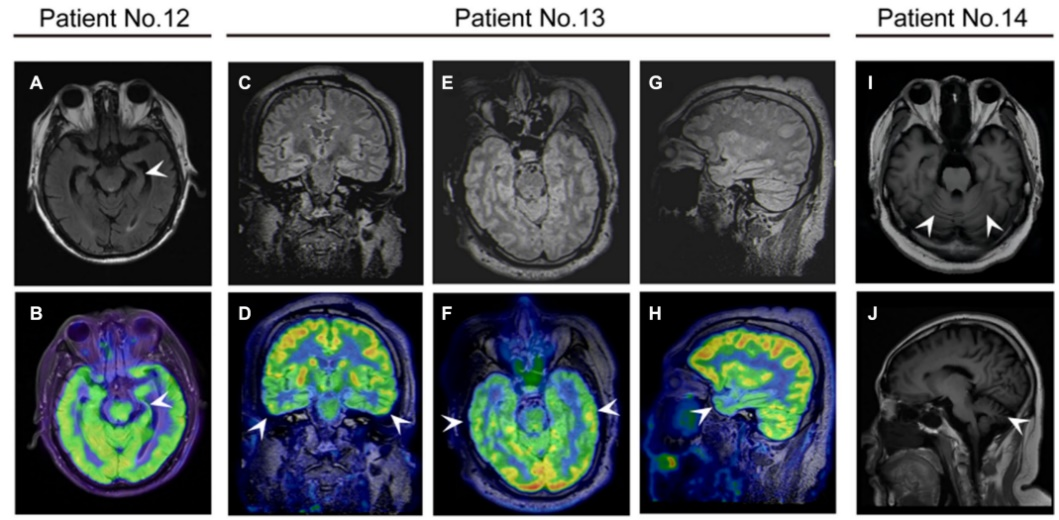

¿¹DPPXÄÔÑ×»¼ÕßµÄÉñ¾Ó°ÏñѧÌåÏÖ¡£(A£¬B)12ÀýÈÏÖªÕϰ»¼ÕߴʲÕñ³ÉÏñ(MRI)ÏÔʾ×ó²àº£ÂíήËõ£¬Õýµç×Ó·¢Éä¶Ï²ãɨÃèÏÔʾ×ó²àº£Âí18F-·úÍÑÑõÆÏÌÑÌÇ(FDG)ÉãÈ¡ïÔÌ(Õýµç×Ó·¢Éä¶Ï²ãɨÃè)/ºË´Å¹²Õñ³ÉÏñ¡£13ÀýÈÏÖª¹¦Ð§Õϰ»¼ÕßÔÚPET/MRI¹Ú״λ(E£¬F)ÖáλºÍʸ״λ(G£¬H)ÏÔʾ˫²àò¨Ò¶1¡ãF-FDGÉãÈ¡ïÔÌ¡£(1,J)¹²¼Ãʧµ÷»¼Õß14ÀýMRIÏÔʾСÄÔήËõ¡£